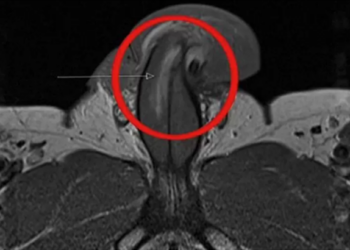

REINO UNIDO | Um homem de 40 anos machucou gravemente o órgão durante uma relação sexual e sofreu uma fratura ...